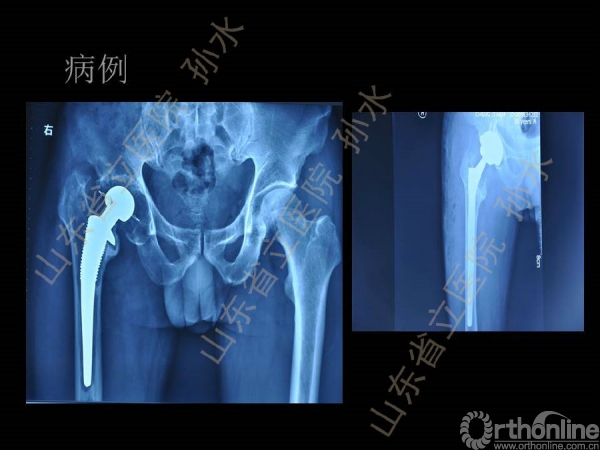

孙水:Jumbo-Cup在髋关节翻修中的应用